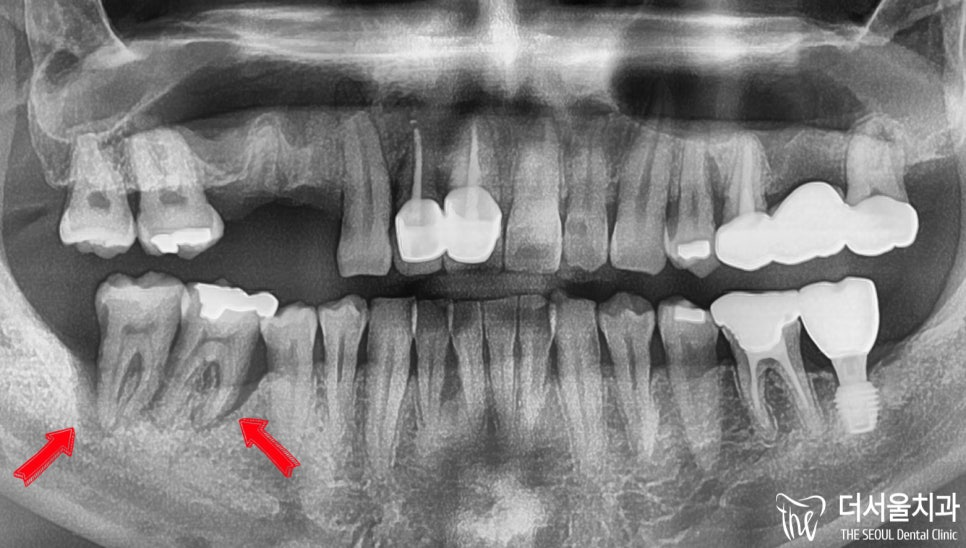

반갑습니다. 잠실 더서울 치과 박현성 원장입니다. 예전에 내원을 하셨던 환자 중에 따님분께 추천을 받아 오게 되었으며, 임플란트 수술을 받았던